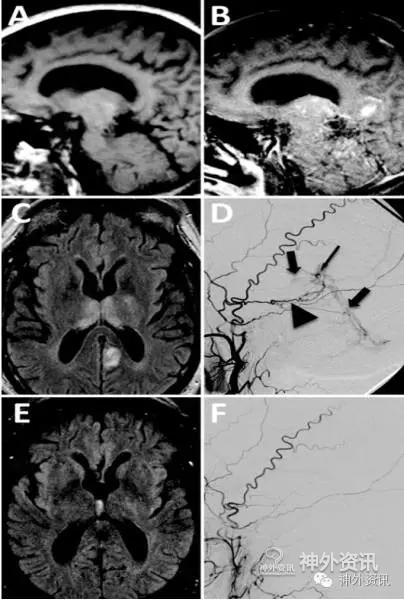

图1. A.颅脑MRI-T1加权矢状位像平扫显示无异常信号;B.颅脑MRI-T1加权矢状位增强像扫描示丘脑强化;C.FLAIR像显示双侧丘脑内侧高信号;D.左侧颈外动脉造影提示颅内深部dAVF,深静脉引流;E.血管内介入栓塞6周后,MRI-FLAIR像显示双侧丘脑高信号消失;F.左颈外动脉造影示dAVF完全栓塞。

4例患者均为男性,53岁~71岁;症状为记忆功能紊乱和恶化,或智能转换状态改变,于发病后4天至6个月入院。入院时检查,有短期和长期记忆力下降、注意力不能集中、联想面孔失认症、中或重度语言流畅性障碍、理解力降低及情绪不稳。其中1例伴轻微的左侧肢体无力。Kokmen短期简易智能状态量表评分为24/30、30/38不等。MRI影像学检查,T1加权像矢状位增强扫描显示双侧丘脑强化,FLAIR像显示双侧丘脑内侧高信号。DSA示半球深部dAVF,深静脉引流(图1)。1例评定为改良Borden-Shucart分型2S,3例评定为改良Borden-Shucart分型3S。2例行血管内介入栓塞治疗,2例血管内介入栓塞结合手术治疗。治疗后患者的影像学异常和临床症状很快缓解。1例术后3月死于心脏病;其余随访3个月至6个月,Kokmen短期简易智能状态量表评分恢复正常、或达30/30、和34/38;1例术前有轻微肢体无力者症状消失。